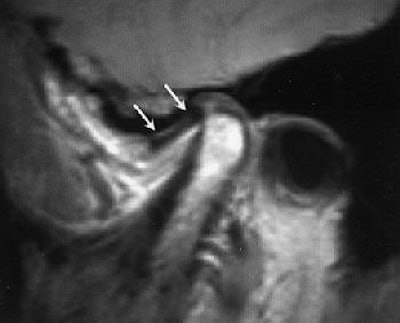

Same patient. Postop lateral displacement of right disk. Pain improved in both joints; clicking resolved in left joint only. Images courtesy of Dr. Jessica Lee.